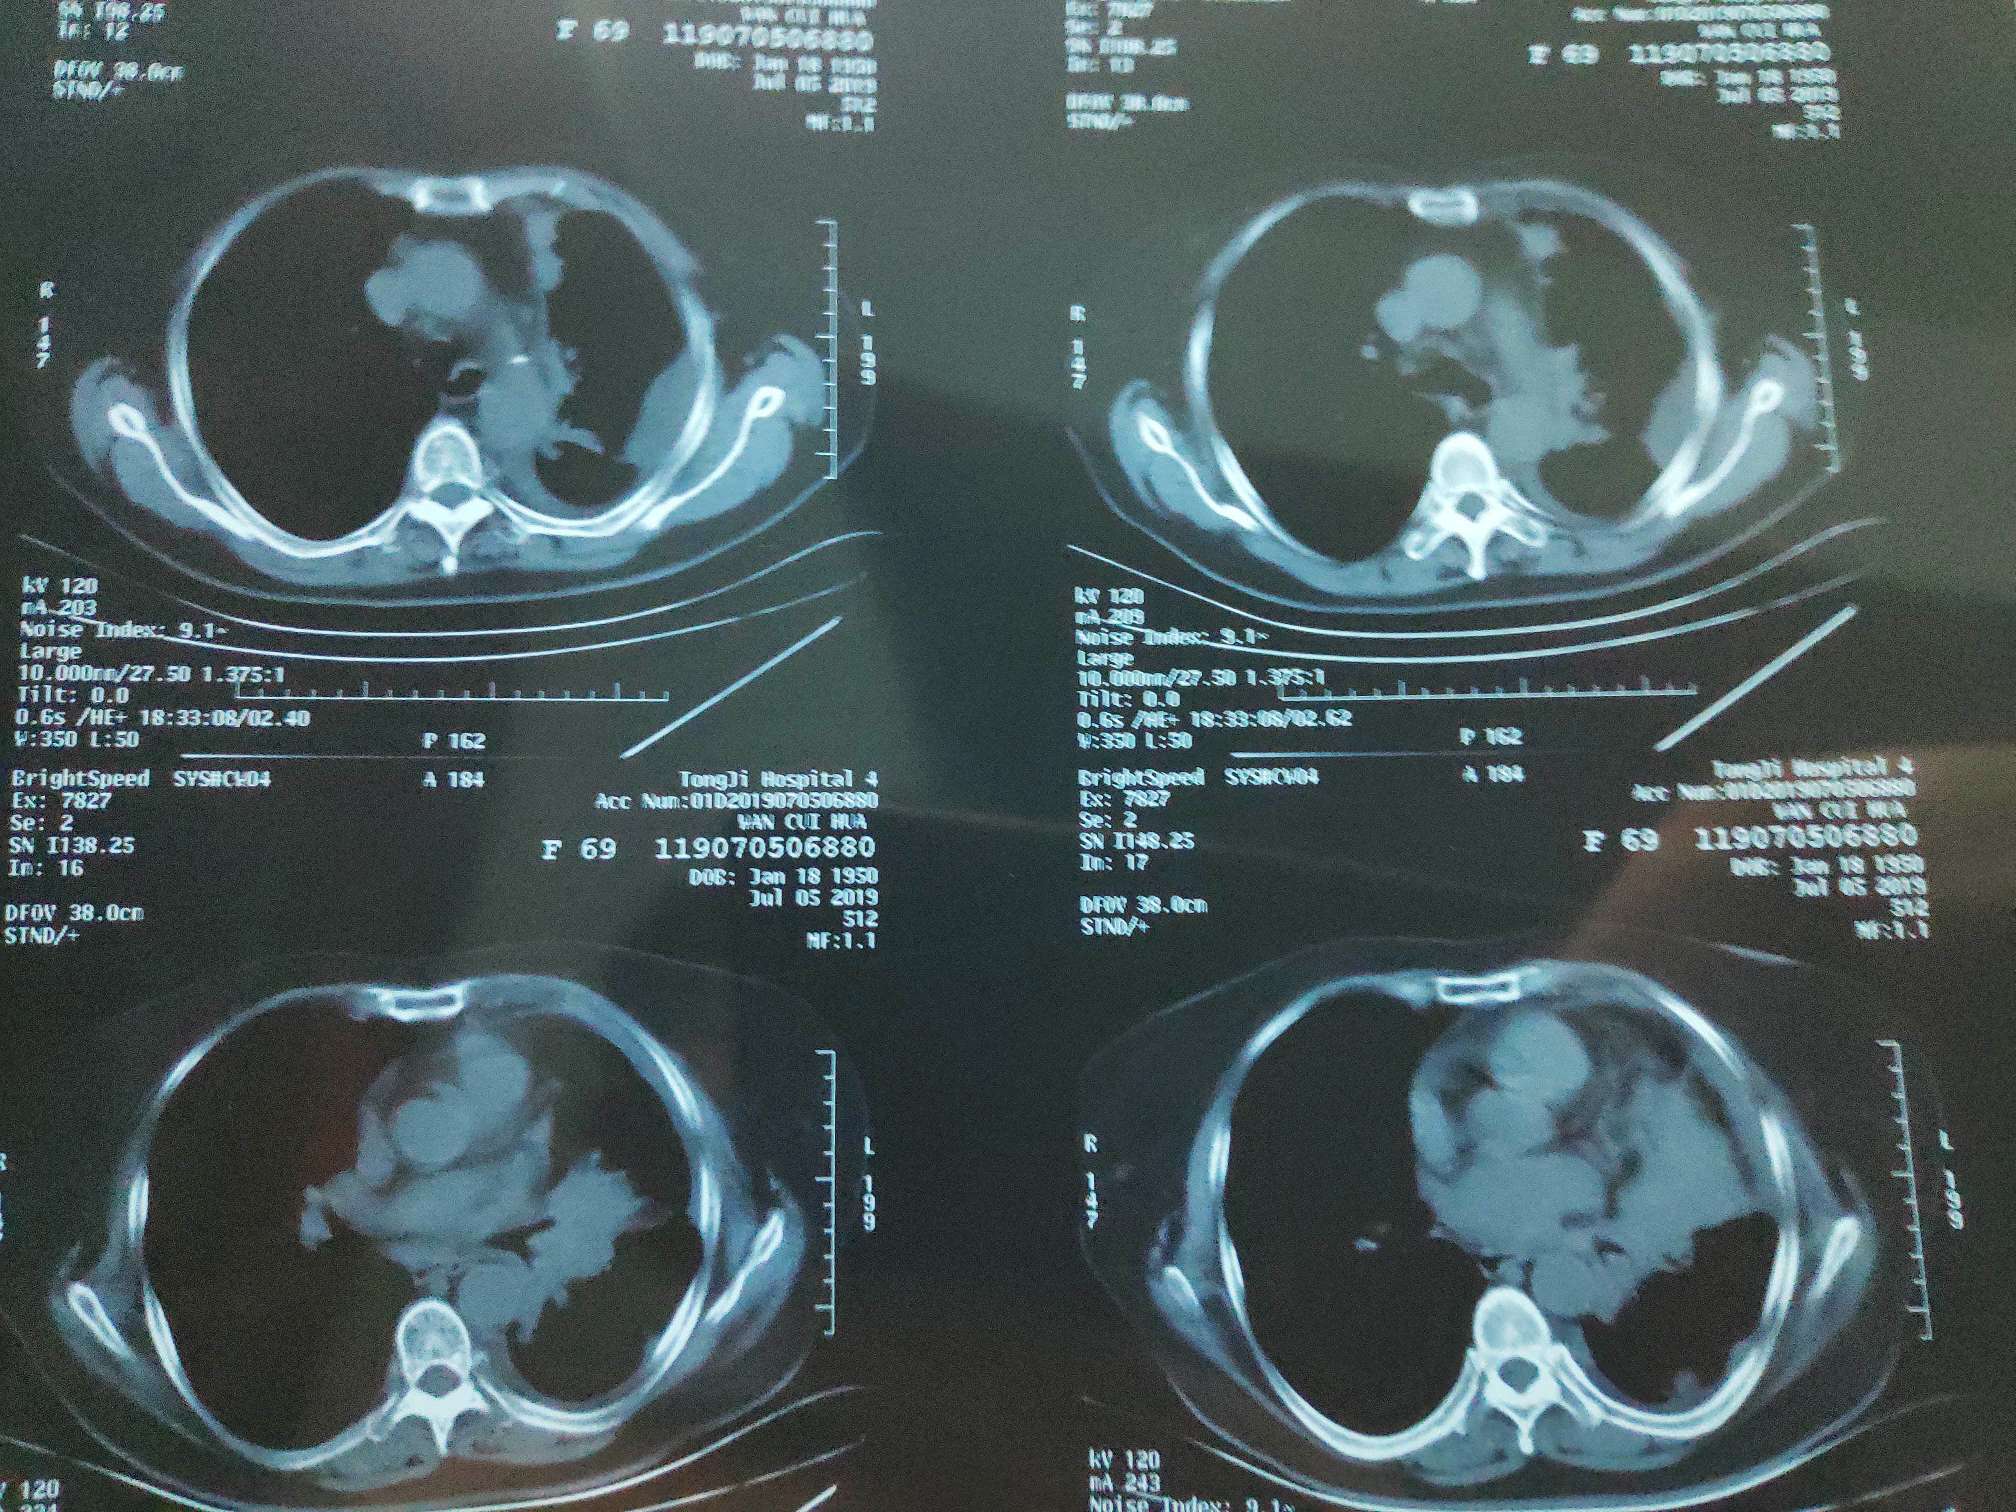

7月5日一化前CT检查,

一化前CT